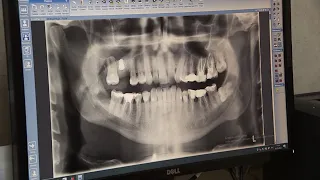

03:10Самое главное – не запускать. Какие проблемы могут доставить зубы мудрости и чем они полезны?CTVBY09.12.2022